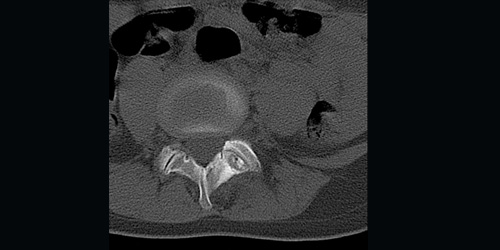

Спинальная метастаза представляет собой распространение рака на кости позвоночника, что часто вызывает боль в спине и другие симптомы. Ранняя диагностика и индивидуально подобранное лечение играют важную роль в улучшении качества жизни и эффективном контроле симптомов.